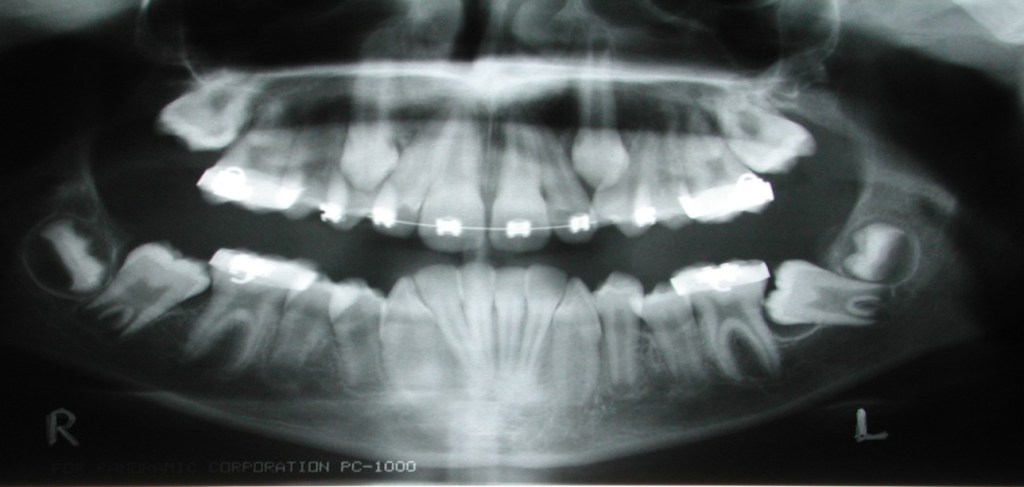

The evaluation of tooth eruption in children starts with the general dentist. Early diagnosis of any eruption disturbance will allow earlier treatment and improved success. Permanent central incisors erupt at ages seven to eight years. Lateral incisors erupt at eight to nine years. Canines erupt at ages nine to 12 years. Premolars erupt at ages 10 to 12 years. Second molars erupt at ages 12 to 13 years. (Fig.1) Identifying the lack of eruption at these time intervals is important so treatment can be initiated early. Full root formation of an impacted tooth makes it more difficult to treat.

Other than third molars, the most commonly impacted teeth are the maxillary canine, maxillary second molars, mandibular second premolars, mandibular second molars and mandibular canine. (Fig.2) The factors that contribute to the impaction of these teeth are arch length discrepancy, space deficiency, ankylosis of primary teeth, pathology and trauma.2

All patients require a thorough clinical evaluation. The radiographic evaluation should include a panoramic radiograph and a 3-D CBCT to evaluate the tooth position and condition of the lateral incisor root. Then, a comprehensive treatment plan can be developed. Informed consent is a must to avoid misunderstanding, which could lead to legal problems. Management of the impacted canine can include one of the following treatment options:

Orthodontic treatment without premolar extractions has become increasingly common due to the possibility of unpleasing facial aesthetic outcomes. This has also contributed to the impaction of the second molar. A panoramic radiograph and a 3-D CBCT is recommended.